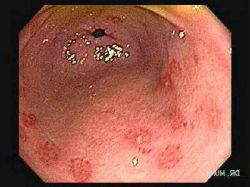

Эрозивный гастрит, симптомы и лечение